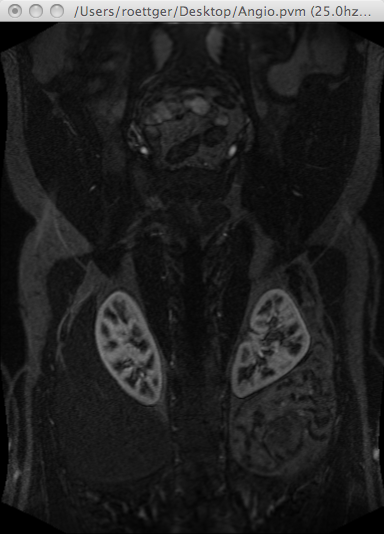

Example MRI angiography scan of a human male body:

http://volume.open-terrain.org/Angio.pvm

Demo display with the $V^3$ pvmplay tool: